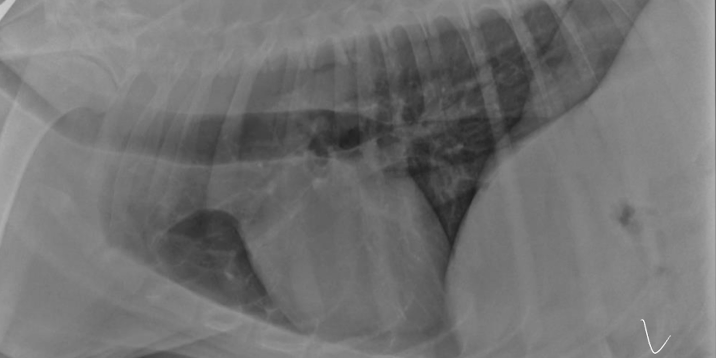

Esophageal dilation